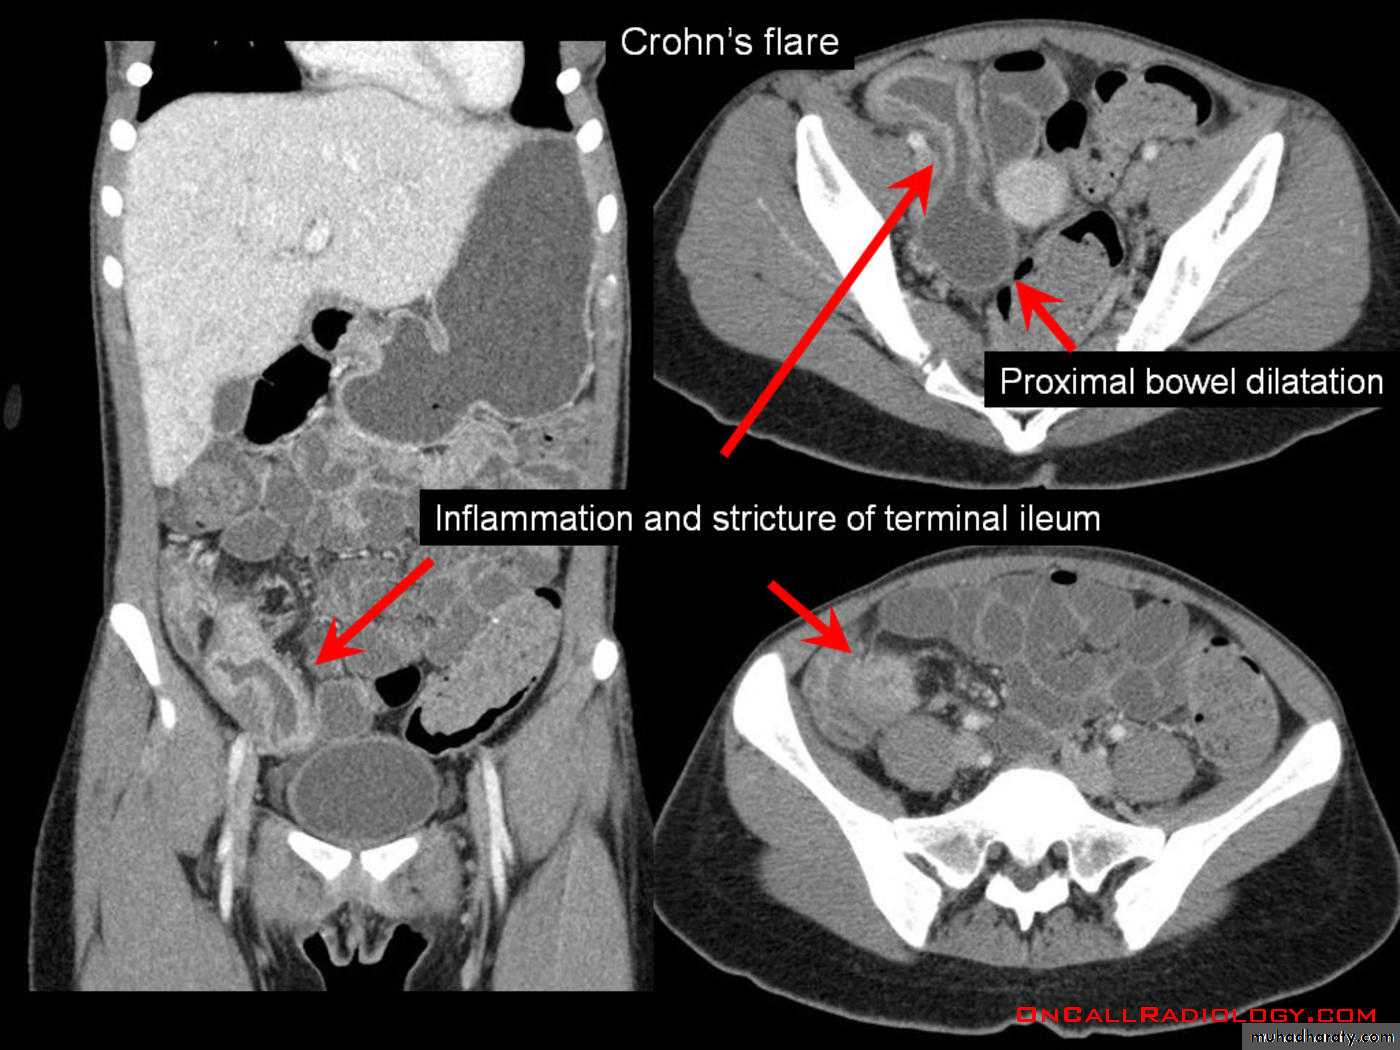

1.Crohn's diseaseis a disease of unknown etiology characterized by localized areas of chronic granulomatous inflammation which Nearly always affects the terminal ileum, it may also affect several parts (skip lesions) of SB & LB with normal intervening parts.

Main signs are strictures & mucosal irregularitya. The strictures (string sign) are variable in length (due to spasm of ulcerated loop or due to oedema & fibrosis of bowel wall) with proximal dilatation. When there is obvious disease of terminal ileum, the caecum may be contracted.

A long segment of narrowed ileum (string sign) is present with proximal ileal dilation& caecal contraction

TI

caecum